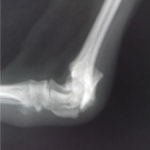

術前レントゲン